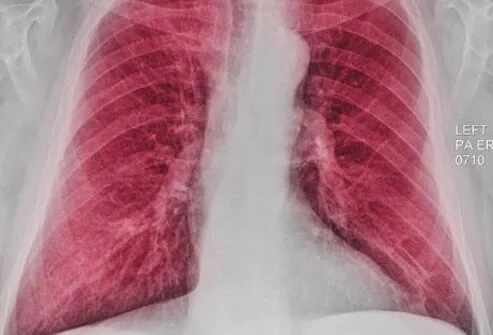

胸部X光

胸部 X 光檢查可能能夠顯示某些COPD患者可能出現的肺部增大(由于過(guò)度充氣)。但是,X射線(xiàn)更有用,有助于排除或排除可能導致類(lèi)似于COPD癥狀的其他問(wèn)題,例如肺炎。